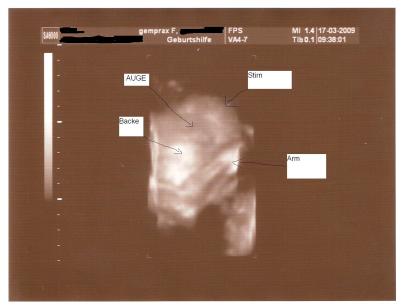

Heute war dann wieder ein Besuch beim Arzt angesagt. Wie immer, mittlerweile ja Routine, mit CTG. Aber hier war Würmchen dafür aktiver und trat die ganze Zeit. Beim Doc selber dann wieder das vertraute Spiel. Um Mama zu ärgern, hat sie/er einfach wieder den Arm vor das Gesicht gelegt, damit ja nicht zu viel preis gegeben wird.